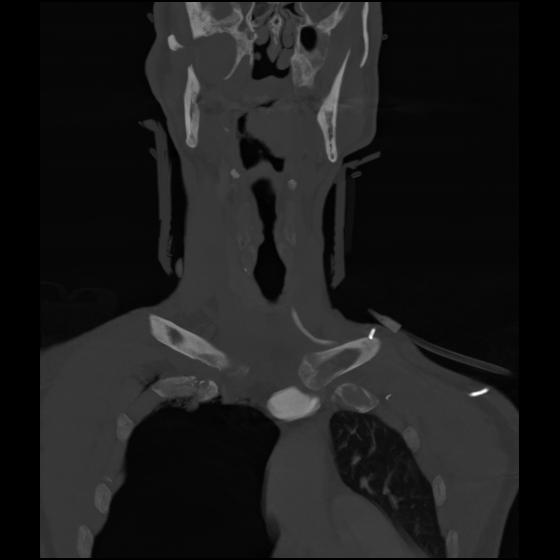

23 ANGIO,CE,Cor-MIP,5.000,ANGIO,Cor-MIP,